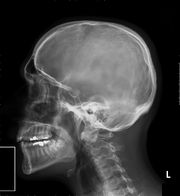

Lékařské využití

Poté, co Röntgen objevil využití pro pozorování kostních struktur, se rozvinulo jeho užívání v lékařském snímkování. Rentgenové záření může být využito pro zobrazení detailů kostí a zubů (skiagrafie), popřípadě za pomoci vhodných technik i ke zkoumání měkké tkáně (denzitografie, subtrakční skiagrafie, tomografie). Radiologie je specializovaný obor lékařství využívající rentgenového záření v diagnostice. Toto je pravděpodobně nejčastější využití rentgenového záření.